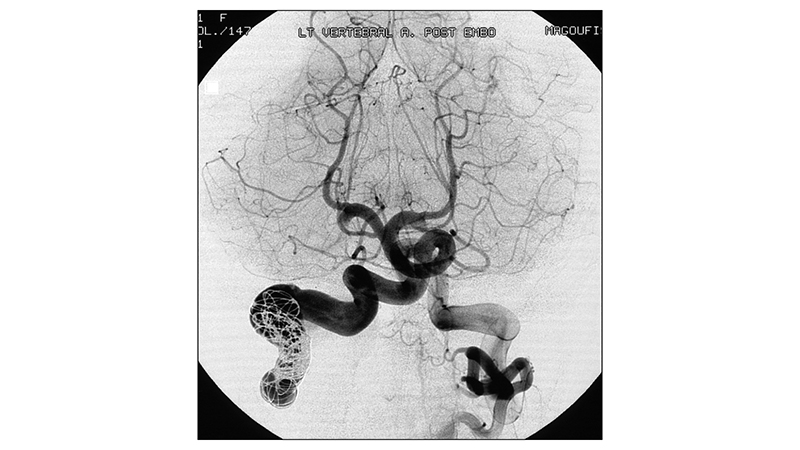

- Με προσπέλαση από την αριστερή σπονδυλική, αποφράχθηκε με coils το A1–A2 τμήμα της δεξιάς σπονδυλικής αρτηρίας, μαζί με το σημείο της επικοινωνίας. Διακρίνουμε την αποκατάσταση της ορθόδρομης ροής στο σπονδυλοβασικό σύστημα με εξάλειψη της υποκλοπής.